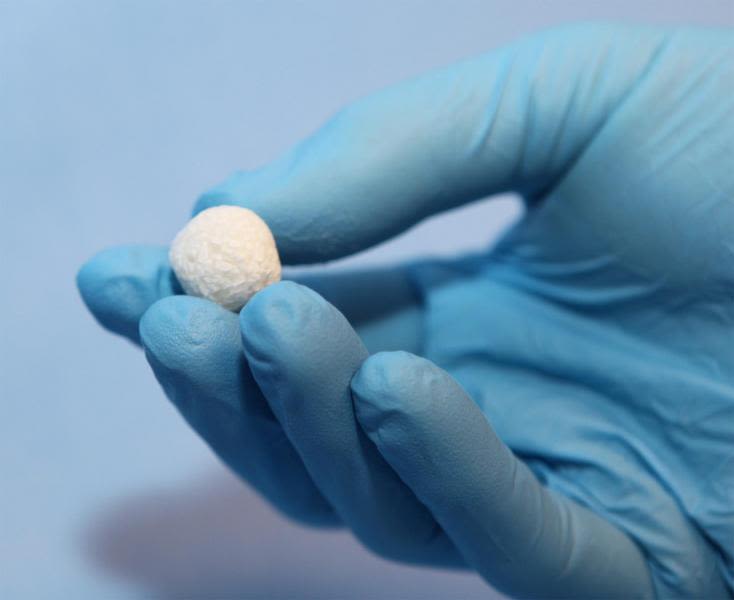

The culmination of the team’s research was the development of a brand new silicate-containing calcium phosphate material with properties much closer to the mineral crystals found in real bone than had been previously achieved in any other synthetic bone graft material. By processing the material to have smaller crystal dimensions and notably smaller pores than other synthetic solutions, the material achieves a much higher surface area, with the result that the surface supports bone repair more effectively and is more readily remodelled than traditional ‘ceramic’ substitutes.

In a pre-clinical comparison with a common commercially available synthetic bone graft substitute it was observed that bone formation when using the newly developed material was significantly faster than the one already in use and that the graft material was successfully resorbed and replaced by new bone. In a more recent regulatory pre-clinical study of the final product, tests showed 100% fusion success after 26 weeks, a remarkable result.